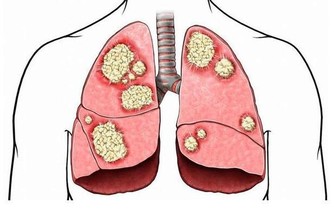

喝水喝得少,就無法排出體內的毒素,時間長了,體內毒素累積,就可能對腎臟造成損傷。腎結石的形成原因之一也是由於水喝的少導致的。

在臨床上,經常能看到患有腎結石的人,但是患者本人往往意識不到,腎結石的常見臨床表現有哪些呢?